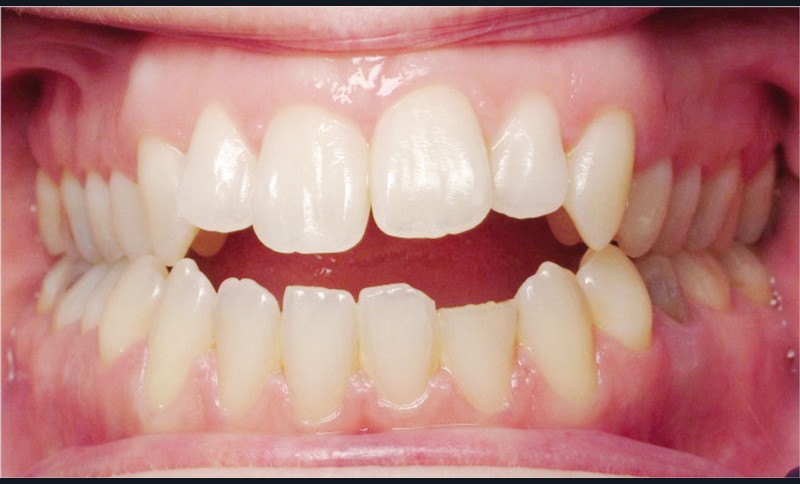

Les empreintes ont été réalisées en sillcone wash technique et adressées au laboratoire Insignia. Actuellement, nous réalisons ces empreintes à l’aide de la caméra intra-orale Lythos et la fiche patient est initialement créée sur la caméra. Le transfert des empreintes au laboratoire est immédiat et le risque d’erreurs considérablement réduit (fig. 4 à 6).